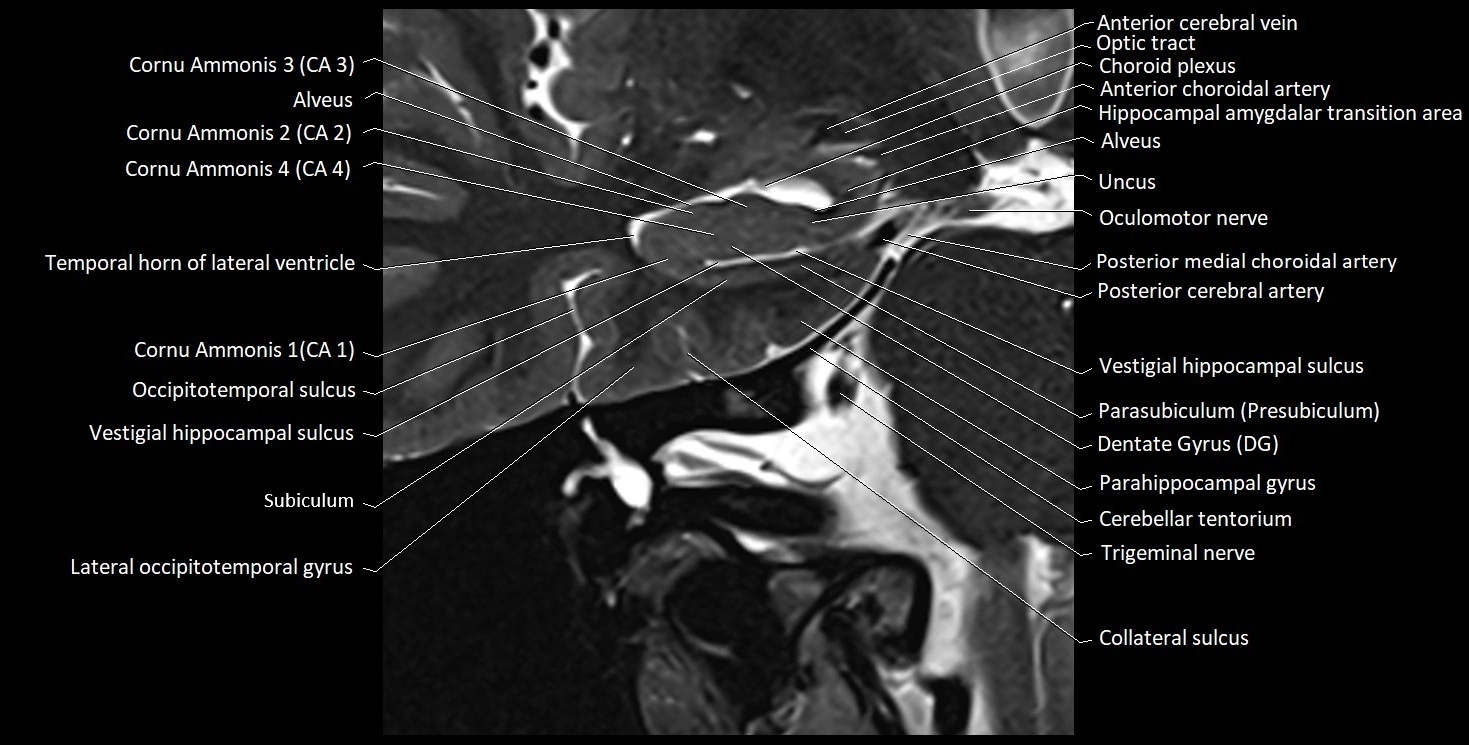

MRI images

image